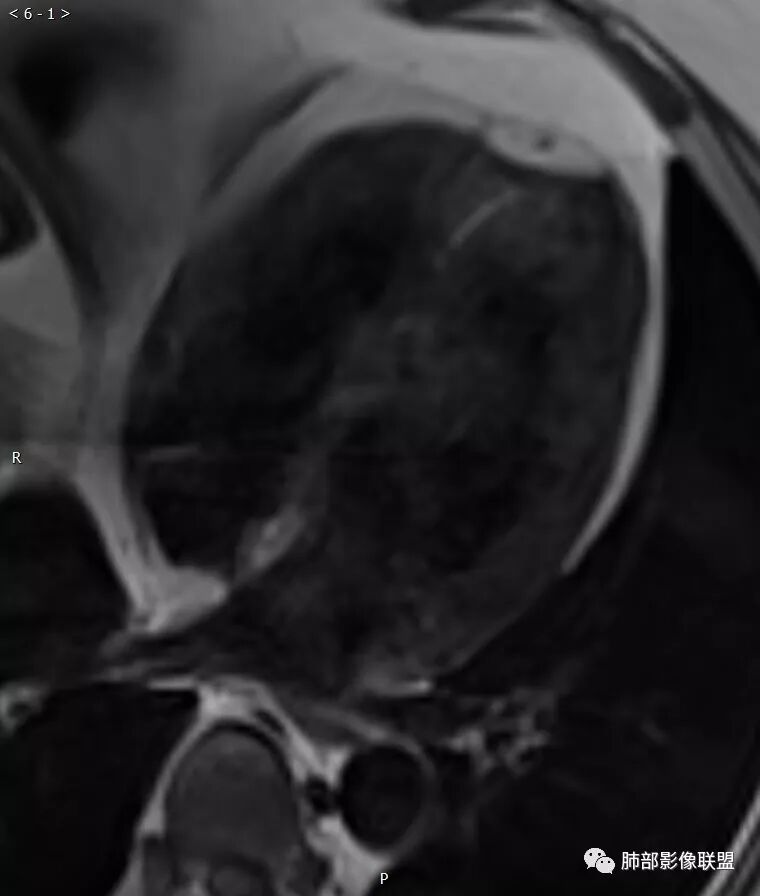

黑血轴位

电影:左室中央段-心尖段下侧壁运动减低,心肌内见片状高信号

T2WI:左室中央段-心尖段下侧壁透壁性心肌片状高信号

首过灌注:左室中央段-心尖段下侧壁心内膜下灌注减低

LGE:左室中央段-心尖段下侧壁透壁性延迟强化

冠心病,左室中央段-心尖段下侧壁透壁性急性心肌梗死并心肌水肿